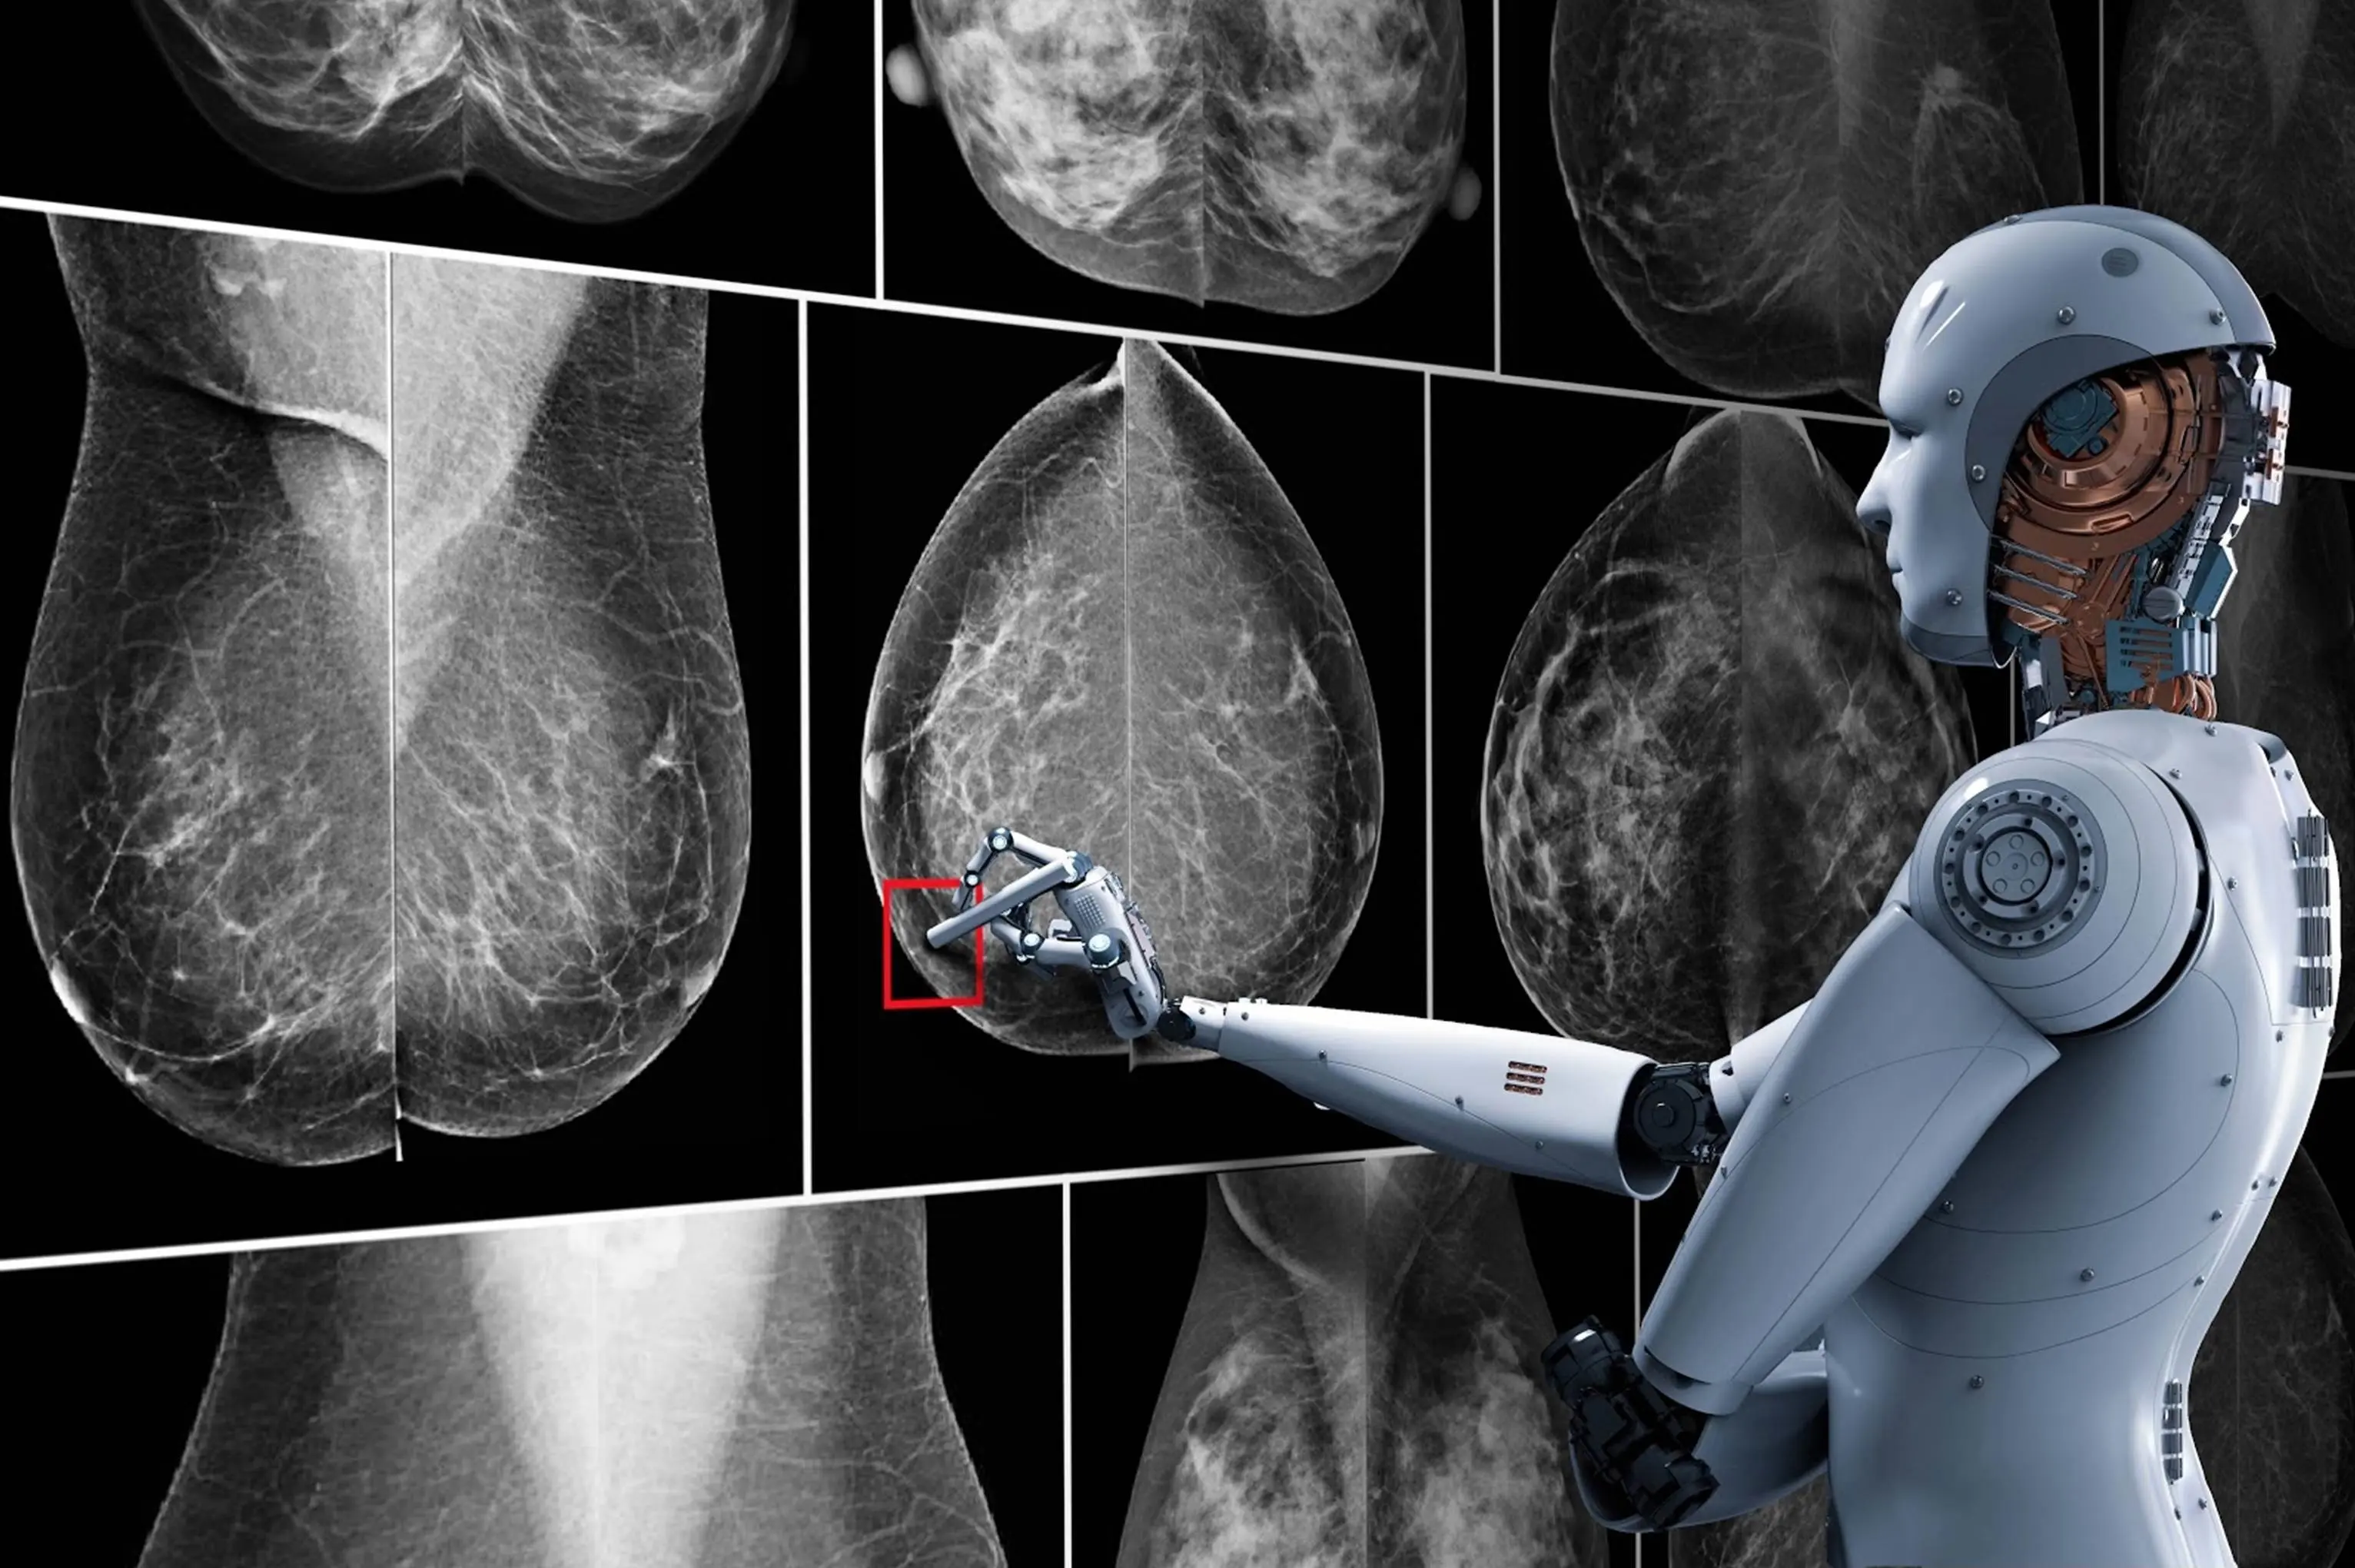

Yapay Zeka Ve Mamografi